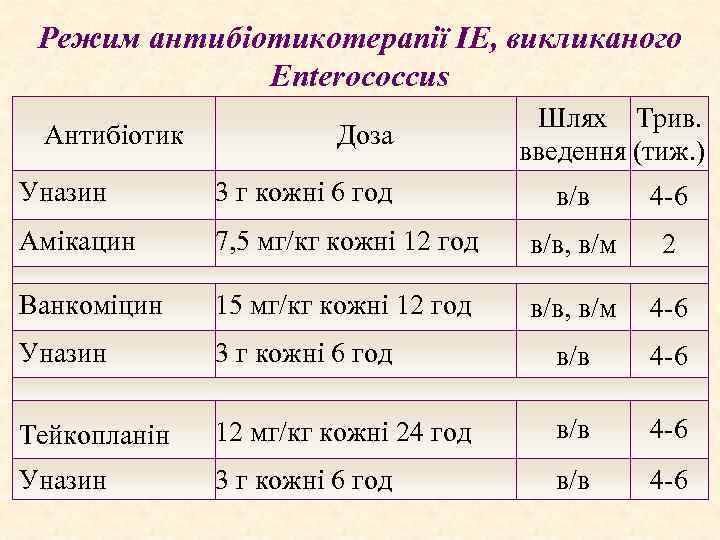

Режим антибіотикотерапії ІЕ, викликаного Enterococcus Антибіотик Доза Уназин 3 г кожні 6 год Амікацин Шлях Трив. введення (тиж. ) в/в 4 -6 7, 5 мг/кг кожні 12 год в/в, в/м 2 Ванкоміцин 15 мг/кг кожні 12 год в/в, в/м 4 -6 Уназин 3 г кожні 6 год в/в 4 -6 Тейкопланін 12 мг/кг кожні 24 год в/в 4 -6 Уназин 3 г кожні 6 год в/в 4 -6